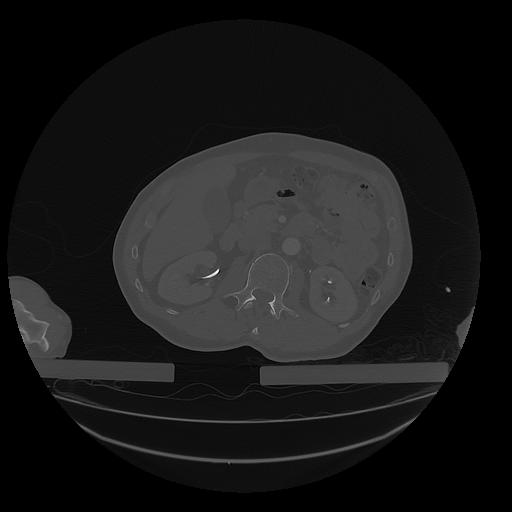

31 PULMON,CE,Vol,1.0,PULMON,,